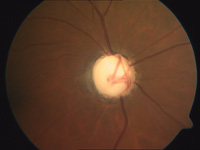

Glaukom (Grüner Star)

Der Grüne Star ist eine Erkrankung, die der Betroffene lange nicht bemerkt. Ein relativ zu hoher Augendruck beeinträchtigt Durchblutung und Funktion des Sehnervs. Es folgen ein fortschreitender Verlust von Sehnervenfasern mit zunehmenden und charakteristischen Veränderungen des Sehnervenkopfes (Papille) sowie die Verengung des Gesichtsfeldes.

Diese Schäden im Gesichtsfeld lassen sich meist erst feststellen, wenn bereits ein Drittel der Sehnervenfasern ausgefallen sind. Eine Heilung im Sinne einer Wiederherstellung des Gesichtsfeldes ist nicht möglich.

Eine spezielle Tomographie des Sehnerven (HRT III-Untersuchung) gibt schon wesentlich früher Aufschluss darüber, ob möglicherweise ein Glaukomschaden vorliegt. Ab dem 40. Lebensjahr sollten Sie deshalb regelmäßig – mindestens alle zwei Jahre – zum Augenarzt gehen. So kann mit Medikamenten oder gegebenenfalls auch mit einer Operation (Lasertrabekuloplatik) ein Fortschreiten des Glaukoms verhindert und wertvolles Sehvermögen erhalten werden.